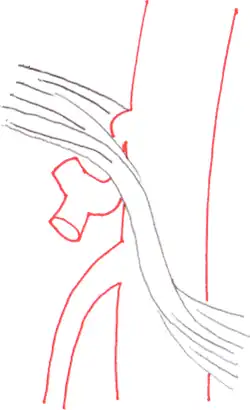

По мнению исследователей, формирование КСЧС связано с особенностями строения и развития аортального отверстия диафрагмы. Аортальное отверстие диафрагмы образуется сухожильными краями правой и левой ножек диафрагмы, соединяющей их срединной дугообразной связкой диафрагмы и телами позвонков. В норме у здорового человека срединная дугообразная связка диафрагмы (СДСД) расположена непосредственно над устьем чревного ствола. Однако у некоторых людей СДСД расположена ниже устья чревного ствола, что приводит к сдавлению сосуда и, как следствие, нарушению в нём кровообращения. На ангиографических снимках таких пациентов можно видеть, как чревный ствол придавлен к брюшной аорте, сужен вблизи своего устья и патологически расширен ниже места сдавления.

Наиболее информативным методом диагностики КСЧС является ангиография сосудов брюшной полости. Сущность метода состоит в том, что в артерию пациента вводится контрастное вещество, которое заполняет сосуд и, блокируя рентгеновское излучение, отображается на рентгеновских снимках. Это позволяет получить рентгенографические изображения чревного ствола и определить наличие и степень его сужения. Разновидностью ангиографии является компьютерно-томографическая ангиография, при которой контрастное вещество вводится в вену. Этот малоинвазивный метод исследования позволяет получить чёткие трёхмерные изображения брюшной аорты и её ответвлений. При экстравазальной компрессии чревного ствола на ангиографических снимках видно, как сосуд сдавлен у основания и прижат к брюшной аорте[1]. В боковой проекции чревный ствол искривлён и изогнут кверху, а по его верхнему краю определяется вдавление. Нижняя стенка сосуда не деформирована, а дистальнее стеноза определяется постстенотическое расширение[5]. Иногда ангиография позволяет визуализировать сдавливающую сосуд серповидную связку или ножку диафрагмы.